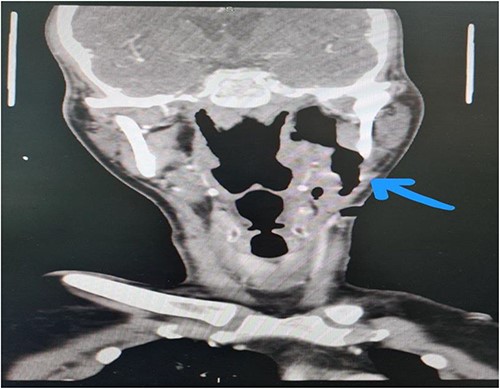

Patient was evacuated to our center 3 weeks after his initial admission. He had a hoarse voice and could not tolerate oral feeding as food would leak from his left side of his neck with choaking episodes. Therefore, the admission diagnosis to our hospital was left pharyngo-cutaneous fistula following parapharyngeal and left peritonsillar abscess drainage and debridement. Clinical examination showed a left 3 × 2 cm peritonsillar wound with mild discharge. In the neck, he had a left sided 3 × 3 cm wound with mild discharge (Fig. 1). A probe was inserted from left neck wound and was almost reaching the left peritonsillar wound. A flexible fiber optic nasoendoscopy was done for the patient and showed a clear patent airway with left vocal cord immobility. Contrasted CT neck was done in our center and showed an almost complete resolution of the left parapharyngeal and peritonsillar abscess with expected postsurgical changes with a non-drainable subcutaneous fluid collection with peripherally enhancing walls located at the subcutaneous tissue of the left antero-lateral aspect of the neck tracking into the area of the thyroid, the collection measured 3.3 × 0.5 × 5.3 cm with evident fistula from the left peritonsillar area to antero-lateral aspect of the neck (Fig. 2).

Contrasted neck CT showing fistula from the left peritonsillar area to antero-lateral aspect of the neck with a non-drainable subcutaneous fluid.